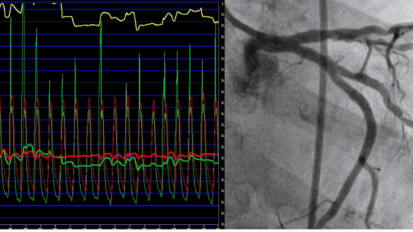

This video is a case review with Dr. Seto discussing vessel disease with iFR Co-registration.

iFR Co-registration cases